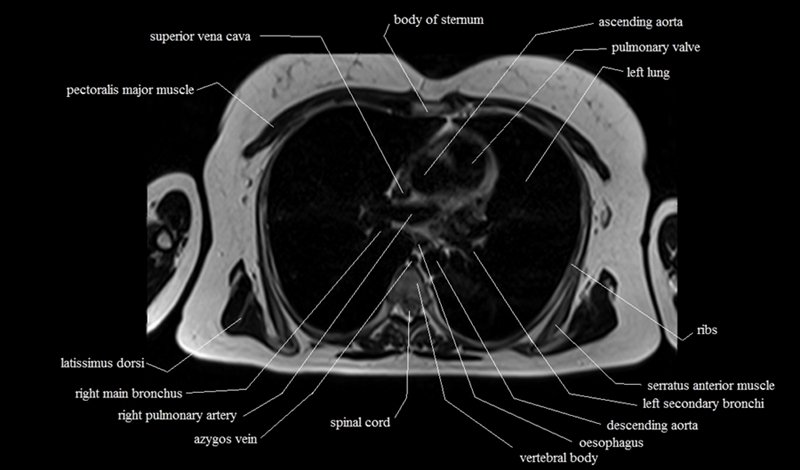

MRI Axial Cross Sectional Anatomy of Chest

This MRI chest (thorax) axial cross sectional anatomy tool is absolutely free to use. Use the mouse scroll wheel to move the images up and down, or alternatively, use the tiny arrows (→) on both sides of the image to navigate through the images. For a more detailed view, double-click the image to view it in full screen, and use the menu in the top right-hand corner to view individual slides or play them in a loop.